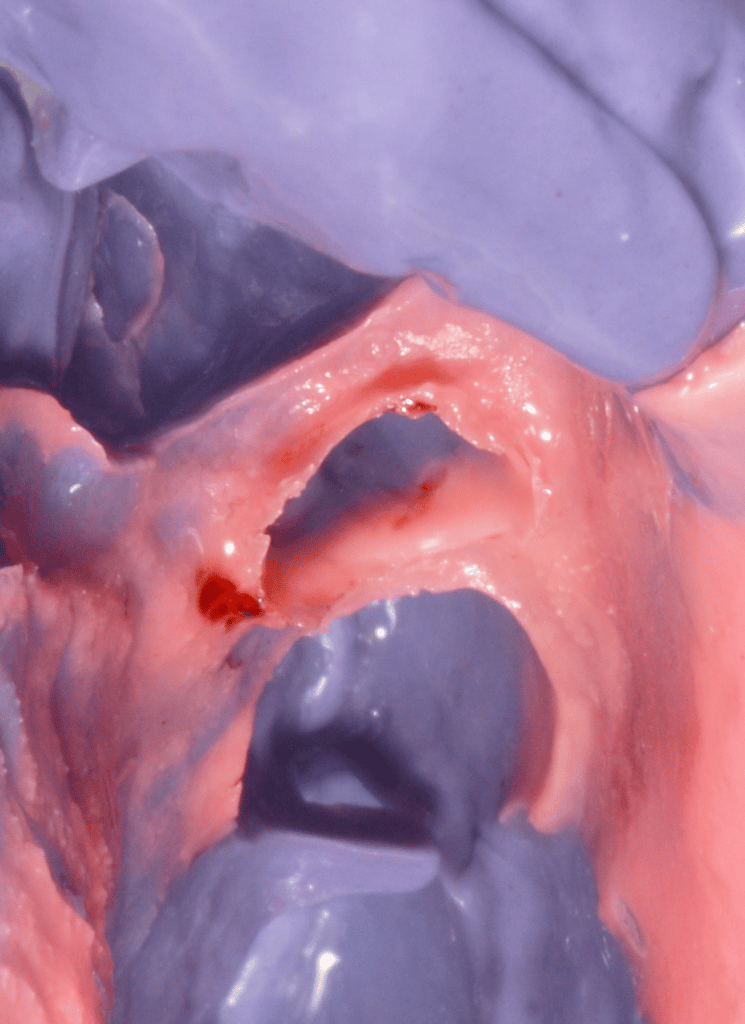

A final champfer preparation is obtained with a subgingival margin of 0.5mm.

During the prep great attention is given to soft tissues.

With a 000 retraction cord the prep is finished slightly under the sulcus.

No bleeding is present and an immediate, final impression can be obtained using single phase putty and light Polyether impression material.

final impression